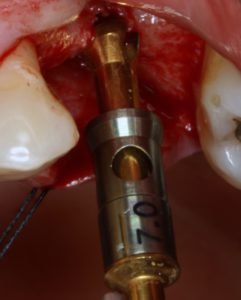

Figura 4: fresa neurológica do sistema SCA realizando a perfiração pela crista do rebordo;